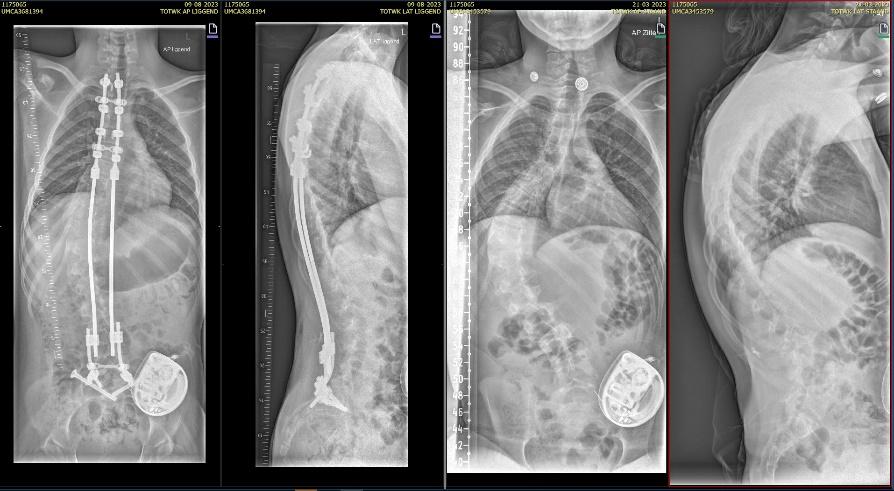

De precieze ingreep, met name hoeveel wervels er worden vastgezet, bepaalt de orthopedisch chirurg aan de hand van rontgenfoto’s.

Als de voorbereidingen klaar zijn begint de operatie. De orthopedisch chirurg hangt kleine gewichtjes aan je benen en hoofd zodat je goed recht ligt. Hiervoor plaatsen we een klem net boven je oren, na de operatie is deze weer verwijderd maar heb je twee kleine gaatjes.. De orthopedisch chirurg maakt een of twee wond(en) op de rug. Tijdens de operatie maakt de chirurg de bocht in jouw wervelkolom zo recht mogelijk. De wervelkolom wordt vastgezet met behulp van titanium staven (of kobalt chroom) en schroeven of haakjes.

Bij neuromusculaire scolioses wordt er over het algemeen gekozen voor een “bipolair systeem”

Bij deze operatie zetten we de wervelkolom vast door middel van 2 verankeringspunten aan de ruggenwervels, boven tussen de schouderbladen en onder in het bekken. Hiervoor maken we een wond tussen de schouderbladen, onderin bij de lage rug, en ter hoogte van het bekken 2 kleine wondjes. De twee verankeringspunten verbinden we met elkaar door een metalen staaf onder de huid te schuiven. Met de staven kunnen we de rug rechter maken.

Rontgen foto voor (links) en na (rechts) scoliose correctie